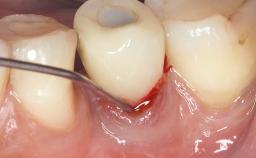

Surgical Management of Peri-Implantitis: Open-Flap Debridement with Seven-Year Follow-up After Treatment

This case describes both a surgical and an anti-infective approach for the management of peri-implantitis, including treatment of the entire dentition to eliminate any deep periodontal pockets that could serve as reservoirs for bacterial re-colonization at the implant site. A 65-year-old female patient was referred to the periodontist in 2013 for assessment and management of an infection at implant 12. On examination, probing depths at implant 12 were 11 mm with suppuration and bleeding on probing.